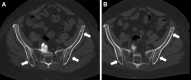

Purpose To determine whether photon-counting CT (PCCT) acquisition of whole-body CT images provides similar quantitative image quality and reader satisfaction for multiple myeloma screening at lower radiation doses than does standard energy-integrating detector (EID) CT. Materials and Methods Patients with monoclonal gammopathy of undetermined significance prospectively underwent clinical noncontrast whole-body CT with EID and same-day PCCT (August-December 2021). Five axial scan locations were evaluated by seven radiologists, with 11% (eight of 70) of images including osteolytic lesions. Images were shown in randomized order, and each reader rated the following: discernibility of the osseous cortex and osseous trabeculae, perceived image noise level, and diagnostic confidence. Presence of lytic osseous lesions was indicated. Contrast-to-noise ratio (CNR) and signal-to-noise ratio (SNR) were calculated. Comparisons were made using paired t tests and mixed linear effects models. Results Seven participants (four women) were included (mean age, 66 years ± 9 [SD]; body mass index, 30.1 kg/m2 ± 5.2). Mean cortical definition, trabecular definition, image noise, and image quality scores were 83, 67, 75, and 78 versus 84, 66, 74, and 76 for EID and PCCT, respectively (P = .65, .11, .26, and .11, respectively). PCCT helped identify more lesions (79% [22 of 28]) than did EID (64% [18 of 28]). CNRs and SNRs were similar between modalities. PCCT had lower radiation doses than EID (volume CT dose index: EID, 11.37 ± 2.8 vs PCCT, 1.8 ± 0.6 [P = .06]; dose-length product: EID, 1654.1 ± 409.6 vs PCCT, 253.4 ± 89.6 [P = .05]). Conclusion This pilot investigation suggests that PCCT affords similar quantitative and qualitative scores as EID at significantly lower radiation doses. Keywords: CT, CT-Spectral, Skeletal-Axial, Spine, Hematologic Diseases, Whole-Body Imaging, Comparative Studies Supplemental material is available for this article. © RSNA, 2022.